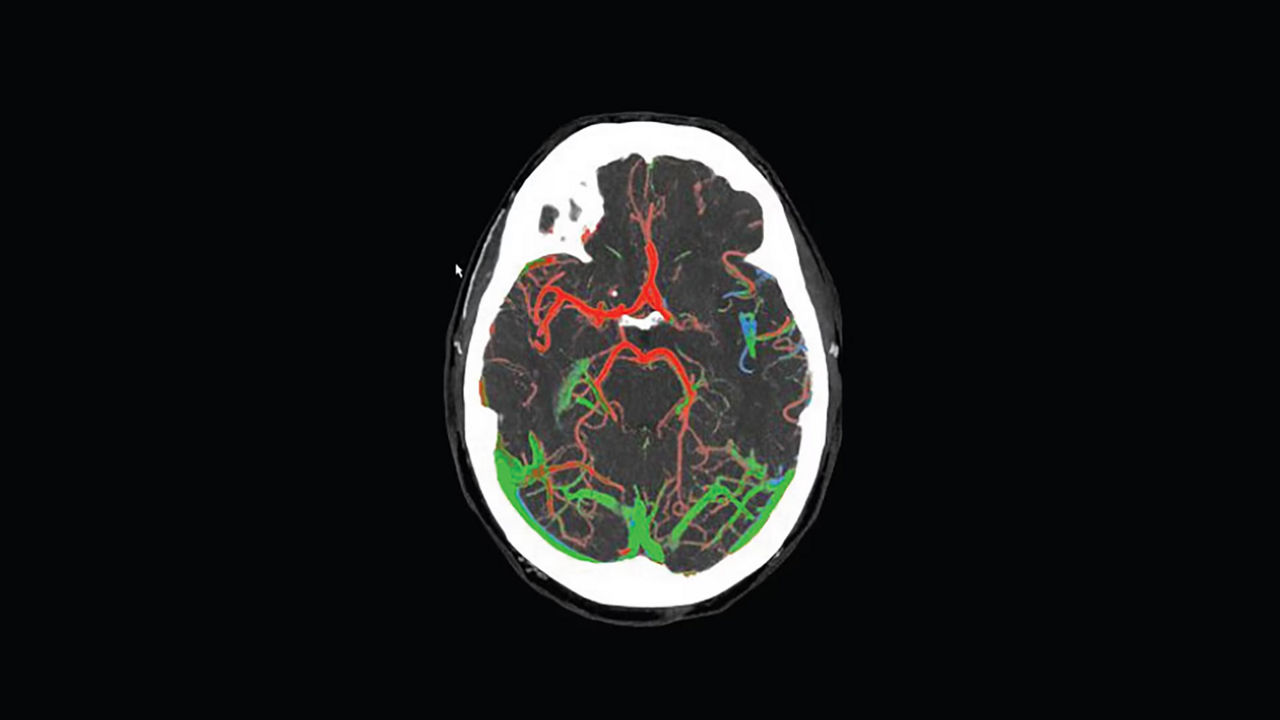

Simplify the Stroke CT workflow and the communication within the stroke team.

<p>FastStroke with StrokeSENS<sup>3</sup></p>

Learn more

<p>CT Perfusion 4D Neuro</p>

<p>Dynamic Shuttle</p>